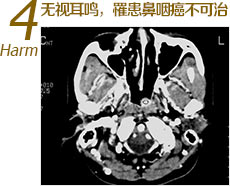

• 无视耳鸣,罹患鼻咽癌不可治

耳鸣可能是鼻咽癌新生物堵塞患侧咽鼓管口。听力降低也可能是鼻咽癌进一步恶化损伤听力神经所致。患者常不在意耽误治疗…[更多危害]